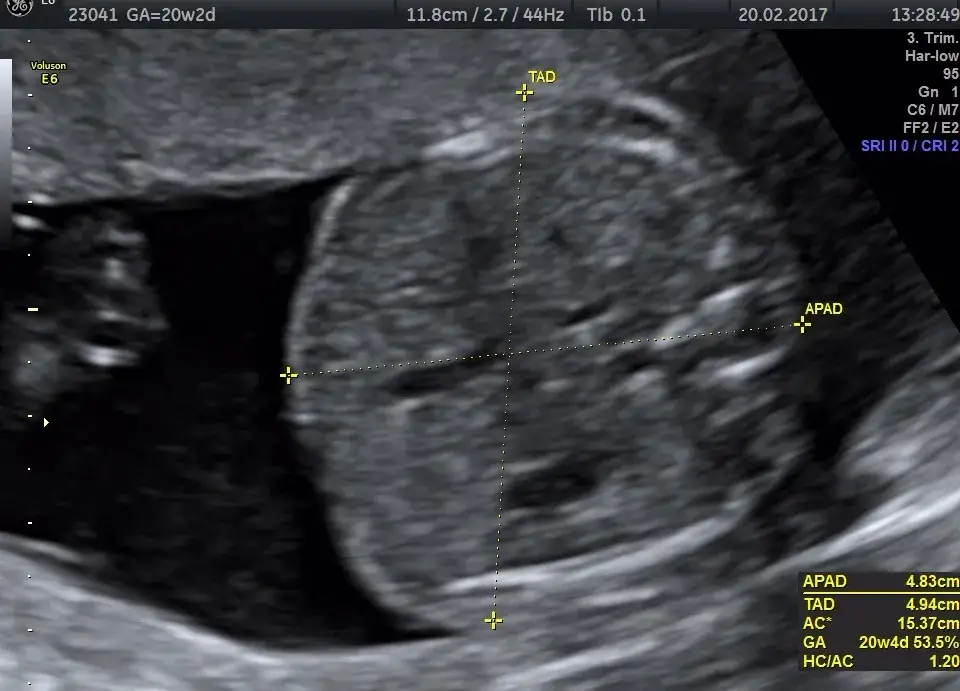

Badanie połówkowe, znane również jako USG połówkowe, jest ultrasonografią, która odbywa się zazwyczaj między 18 a 22 tygodniem ciąży. Jego głównym celem jest ocena rozwoju płodu oraz identyfikacja ewentualnych nieprawidłowości. To badanie jest kluczowe dla oceny zdrowia dziecka i może dostarczyć informacji o jego rozwoju anatomicznym.

Podczas badania lekarz analizuje różne struktury ciała płodu, takie jak serce, mózg, nerki i inne organy. Dzięki temu można wykryć wady wrodzone lub inne problemy zdrowotne. Wczesne wykrycie takich nieprawidłowości może pozwolić na podjęcie odpowiednich działań medycznych, co jest niezwykle istotne dla przyszłego zdrowia dziecka.

Podczas badania połówkowego lekarze poszukują różnych informacji, które mogą pomóc w ocenie zdrowia płodu. USG połówkowe pozwala na dokładne zbadanie anatomii dziecka, a także na identyfikację ewentualnych nieprawidłowości. Specjaliści zwracają uwagę na rozwój organów wewnętrznych, takich jak serce, nerki i mózg, a także na ogólny stan zdrowia płodu. Wyniki badania mogą ujawnić zarówno normalne, jak i niepokojące zmiany.